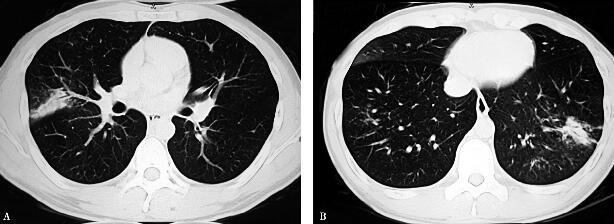

24小时后体温下降。咳嗽减轻,痰易咳出,头痛及四肢肌痛基本缓解。酶学检查:恢复正常。胸部CT表现(2008年7月1日):病灶明显吸收(图3A右肺中叶斑片影、B左肺下叶斑片影)。

图3